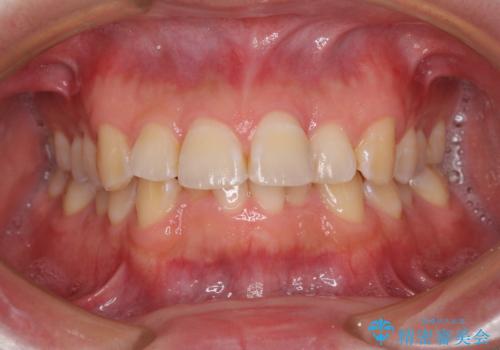

上下前歯の叢生をインビザラインできれいに

担当医 藤巻太一朗